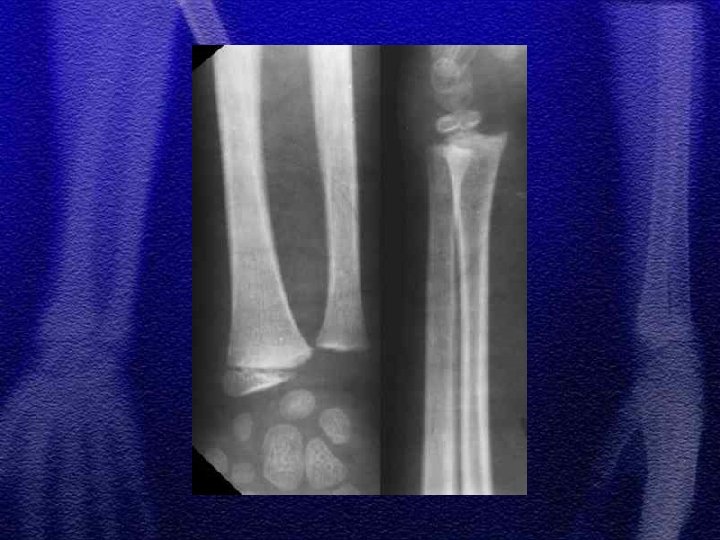

§ Złuszczenia nasady bliższej wyjątkowo rzadkie, obarczone powikłaniem pod postacią zaburzenia wzrostu kończyny co może prowadzić do znacznych odchyleń osi § Złamania bliższej przynasady mogą powodować podobne powikłania

§ U dzieci małych mogą wystąpić kłopoty diagnostyczne, ponieważ obrzęk w obfitej w tkankę tłuszczową kończynie jest niezauważalny, dziecko raczkuje, przy złamaniach podokostnowych lekko utyka chodząc, dlatego zdarza się że rozpoznanie jest opóźnione § Leczenie - gips udowy 2 -4 tyg. § U dzieci zdarzają się, choć rzadko, złamania marszowe

§ Leczenie zachowawcze jest zasadniczym postępowaniem, niezależnie od wieku dziecka § Dopuszczalne skrócenie odłamów do 1 cm § Dopuszczalne załamanie osi do 10° § Dopuszczalne przemieszczenie do boku o 2/3 szerokości trzonu

§ Przy wtórnych przemieszczeniach kątowych stosuje się gipsotomię § Leczenie operacyjne: złamania otwarte, złamania niestabilne - ZESPOL, śruby, stabilizatory zewnętrzne

§ W zależności od mechanizmu urazu spotykamy różne typy złuszczeń od I do IV wg Saltera-Harrisa § Złuszczenia typu I i II leczenie zachowawcze gips - 4 tyg. § Złuszczenie typu III i IV leczenie operacyjne - śruby, druty Kirschnera § Złuszczenia wielopłaszczyznowe typ II i III występujące jednocześnie w nasadzie dalszej kości piszczelowej